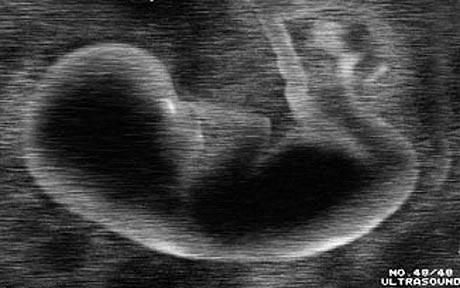

三天大的人体胚胎

实验四:将跟踪剂插入人体胚胎监测它是如何发育的。

前提:孕妇要进行详细的测试以保证胎儿是正常的。任何人都不想科学家将他们的孩子当做实验对象。但倘若没有这种激进的试验,我们可能无法完全理解人类发展未解开的谜题:一个微小的细胞是如何发展成完全的人类。目前科研学者具有追踪细胞基因活动发展的工具。为了追踪胚胎细胞内不同基因的活性,科学家可以将合成病毒插入到视觉检测的“记录”基因(绿色荧光蛋白),随着细胞分裂和分化,研究学者可以观测到基因在发展过程中是如何起作用的。

代价:完全标记胚胎可以让我们更好地成人。这将帮助科学家将干细胞的进化用于直接修复细胞损伤和治疗疾病(也就是将健康的神经元插入帕金森氏症患者的大脑里)。通过对比人类与其它生物的发展细节,科学家可以了解两者之间,决定诸如语言这样复杂属性的重要遗传表达的差异。